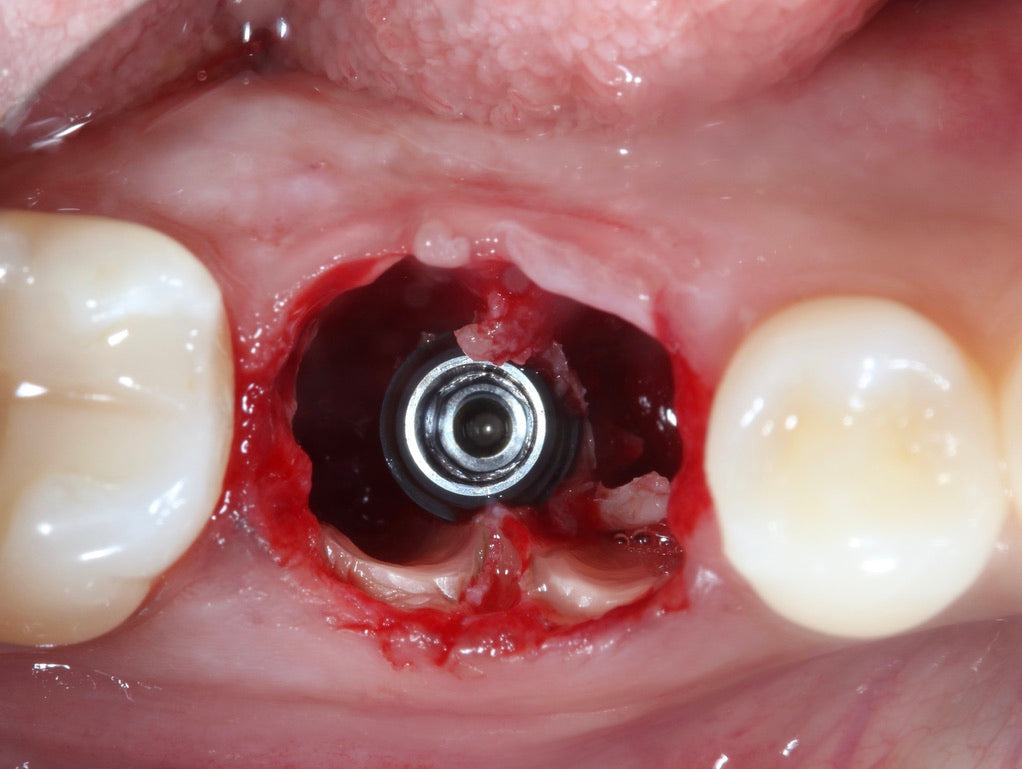

- Socket shield,

- Root submergence,

- Socket shield modifications